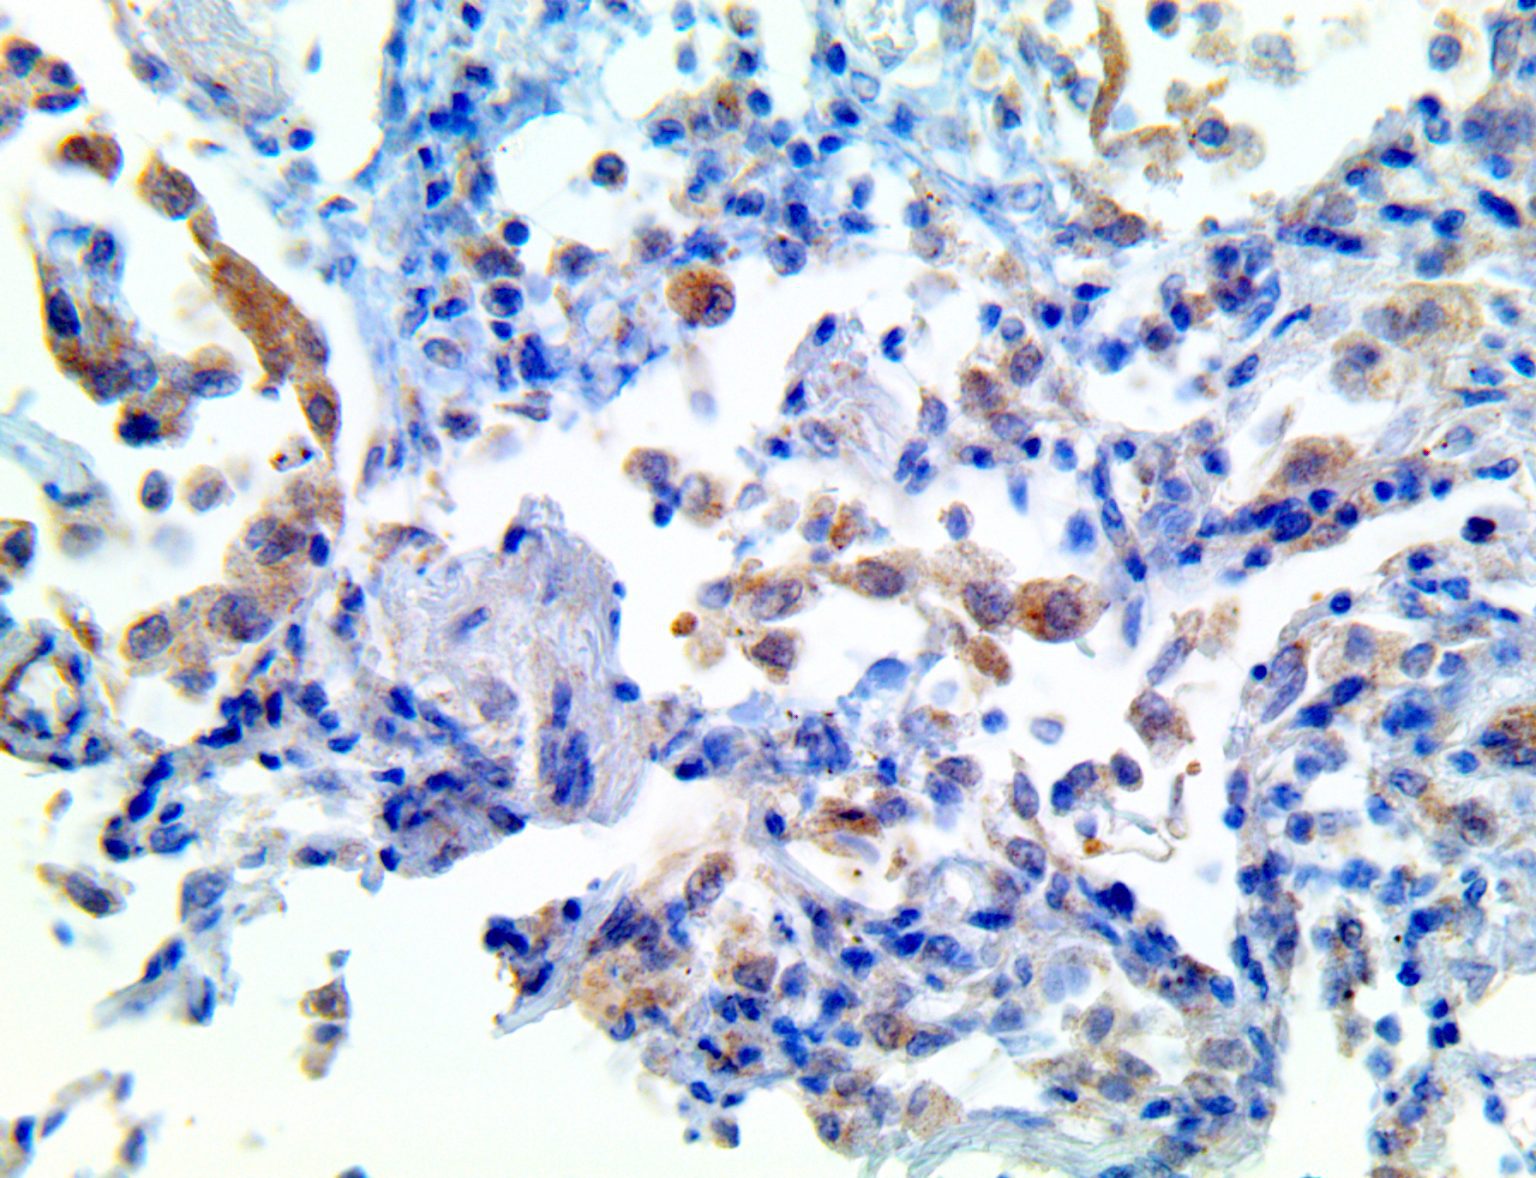

It is the ICU physician who is most likely to witness one of the deadliest manifestations of the abnormal immunological response, the cytokine storm syndrome (CSS). This response is also referred to by some as the cytokine release syndrome (CRS). CSS is characterized by continuous activation and expansion of macrophage and lymphocyte populations, which secrete large amounts of cytokines, causing the cytokine storm. This massive cytokine release is akin to hemophagocytic lymphohistiocytosis (HLH) disease, a syndrome characterized by initial unchecked and persistent activation of cytotoxic T lymphocytes and NK cells.

Clinical and laboratory manifestations of HLH include fever, enlarged liver and/or spleen, neurologic dysfunction, coagulopathy, liver dysfunction, cytopenias (i.e., low levels of erythrocytes, leukocytes, and/or platelets), hypertriglyceridemia, hyperferritinemia, hemophagocytosis, and eventually diminished NK cell activity as the immune system becomes progressively paralyzed. HLH can be familial (primary HLH) or secondary to another disease process (sHLH), such as rheumatic disease, in which it is referred to as macrophage activation syndrome (MAS, characterized by elevated ferritin).

This activation induces inflammatory monocytes to highly express IL-6, starting a localized and then systemic cascade effect that results in hyperproduction of IL-6, which accelerates the inflammatory process. Because IL-6 also increases vascular permeability, excessive levels cause blood vessels to become very leaky. This, along with clotting factors released from vascular endothelial cells, stimulates the coagulation cascade, resulting in microthrombosis (tiny clots), which leads to ischemia and tissue death of the kidney, intestines, heart, liver, brain and extremities.